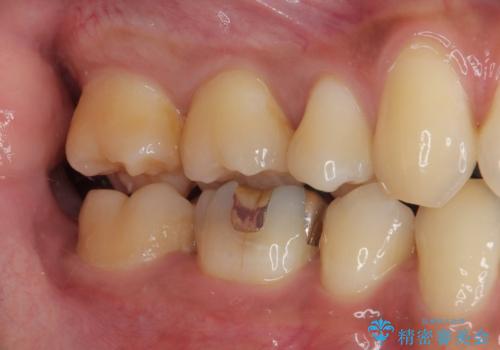

- 銀歯をセラミックにしたいとのことで来院された患者様です。検査の結果、メタルインレーが大きくご自身の歯の残る量を考慮して、オールセラミッククラウンによる補綴治療を行っていくことにしました。

拡大鏡視野下で、メタルインレー、虫歯の除去を行いオールセラミッククラウンに適した形に整えました。